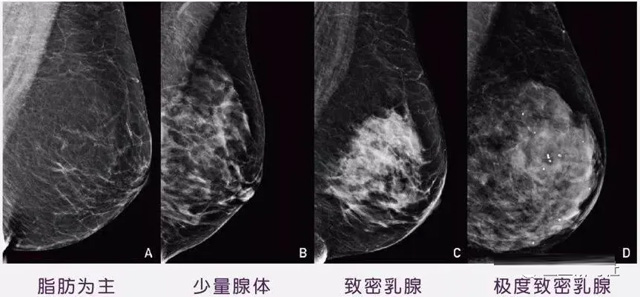

女性乳腺的自我檢查,特別是注意有小結(jié)節(jié),腫塊,乳頭有液體滲出情況,需要通過(guò)乳腺DR,X光線,磁共振等影像技術(shù)檢查。胸的大小跟乳腺癌沒(méi)多大關(guān)系,乳腺的密度大發(fā)病率高一些,胸小脂肪少致密性大。更容易乳腺癌。這個(gè)還不能通過(guò)自我檢查來(lái)確認(rèn)。致密乳腺組織看上去是白色或淺灰色需要通過(guò)乳腺X射線檢查。